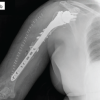

A 47-year-old female, who had undergone bilateral CR total knee arthroplasty (TKA) 2 years prior, for Grade IV osteoarthritis, presented to the emergency department following a fall at home. She was unable to move the affected limb or bear weight on the injured knee since the fall. Clinical examination revealed normal vital signs, an intact peripheral neurovascular status, and healthy overlying skin with localized ecchymosis lateral to the tibial tuberosity. Radiological and hematological investigations were conducted. An X-ray of the knee joint showed a loose tibial component that had sunk into the tibial metaphysis anteriorly, a minimally displaced avulsion of the tibial tuberosity, and a laterally displaced fragment of the lateral tibial condyle (Fig. 1). A fracture line was also observed in the posterior cortex of the tibia. Hematological investigations were within normal limits. Due to the pain and swelling around the knee, it was not possible to fully assess the stability of the knee joint clinically. The patient was thoroughly counseled regarding the possible need for a metaphyseal cone along with a stemmed tibial component or a hinge knee prosthesis. She was also informed about the potential requirement for bone graft harvesting from iliac crest and the necessity of strict bed rest for 1 month if restoration of the primary knee arthroplasty was attempted after reconstructing the tibial bone loss with autogenous bone graft. The surgical plan was to approach the knee joint through the previous incision, using the avulsed tibial tuberosity as a tibial tuberosity osteotomy to enhance exposure of the knee joint. This would allow for an assessment of the bone stock after removing the loose tibial component, before deciding on the further course of management.